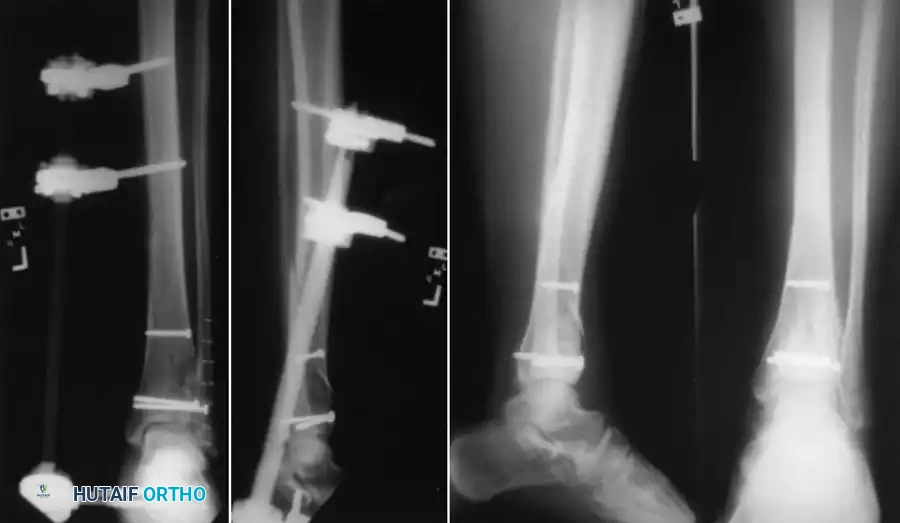

Clinical & Radiographic Imaging